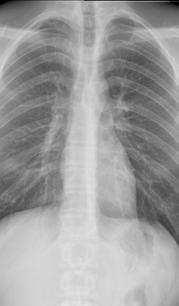

Ook binnen de neurochirurgie zetten geavanceerde beeldvor mingstechnieken de artsen op de juiste weg. Prof. dr. Tomas Menovsky, diensthoofd neurochi rurgie: ‘Een man van 57 werd naar ons doorverwezen omdat hij last had van vermoeidheid, hoofdpijn en verminderde kracht in armen en benen. De CT scan toonde geen duidelijke afwijkingen. We hadden enkel een vermoeden van het pro

bleem op basis van de klachten.’

Om het probleemgebied duidelijk in kaart te brengen, werd uitgewe ken naar een perfusiescan die via contrastvloeistof de doorbloeding van de hersenen in beeld brengt. Menovsky: ‘We interpreteren de beelden altijd samen met de radioloog. Vanuit hun vakgebied zien ze dingen die wij niet zien, en omgekeerd.’ Op de beelden was te zien dat een bepaald deel van

Op het linkerbeeld is te zien dat de bloedvaten in de hersenen meer moeite hebben om de bloedtoevoer in de hersenen te garanderen. Op het beeld rechts, na de operatie, is het probleem hersteld.

de hersenen onvoldoende door bloed was. ‘Op basis daarvan was een bypass de beste behandeling. Tijdens een operatie maakten we een luik in de schedel en verbonden we een slagader van de huid met het deel van de hersenen dat onvol doende doorbloed was. Dat heeft het probleem opgelost voor die patiënt. Met dank aan de precieze beelden. Zonder die beelden was de ingreep nooit mogelijk geweest.’